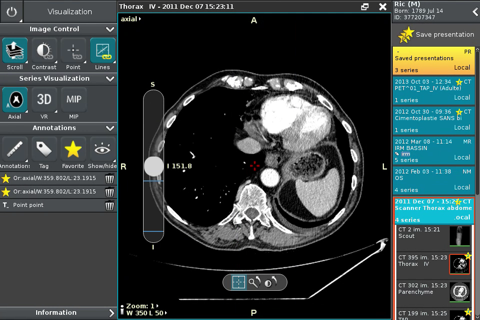

Anywhere Streaming is a DICOM visualization client that connects to Anywhere Server. It provide standard medical image navigation tools surch as : slicing, windowing, MPR, 3D VR, MIP, oblique ... All standard medical image modalities are ...